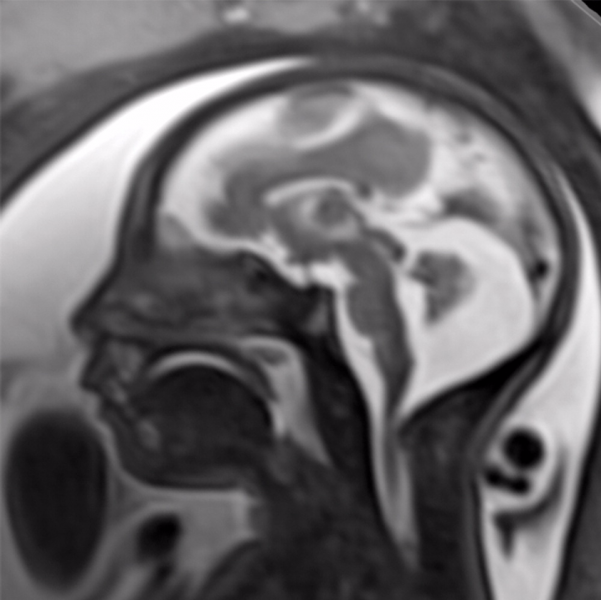

Though much of the concern in the media regarding the toxic effects of Zika virus has focused on brain findings of microcephaly, the researchers noted that there are a variety of brain abnormalities that can be found in fetuses exposed to the virus, including gray and white matter volume loss, brainstem abnormalities, calcifications and a condition called ventriculomegaly, where the ventricles, or fluid filled spaces in the brain, are enlarged. Some babies infected by Zika may not have a small head size if the ventricles remain excessively enlarged.

The brain abnormalities seen in confirmed and presumed Zika groups were very similar. Nearly all of the babies in each group had ventriculomegaly. Although most fetuses had at least one exam showing abnormally small head circumference, the researchers discovered that head circumference was normal in three fetuses with severe ventriculomegaly.

The babies’ skulls frequently had a collapsed appearance with overlapping sutures and redundant skin folds. The researchers believe the unusual appearance of the skull is due to a combination of the small brain as it develops, but also a result of what at some point was likely a larger head size — due to ventriculomegaly — that then decompresses, and/or brain atrophy, giving the skull the collapsed shape.